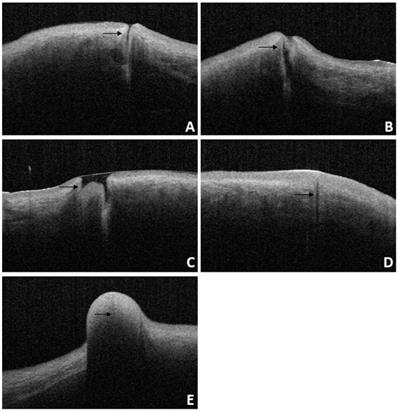

For patients diagnosed with punctal stenosis, OCT showed that the opening of the lacrimal punctum was narrow and small, and the lumen of the vertical canaliculus looked like a fissure. In the case of patients diagnosed with punctal obstruction, OCT showed that the opening of the lacrimal punctum was shielded by a banded membrane-like material, one end was connected to the lacrimal wall, while the other was suspended near the opening of the punctum. Furthermore, the vertical canaliculus was visible. In patients diagnosed with punctal tear, the lacrimal punctum had an abnormal shape, and the opening was larger than normal. In cases of punctal atresia, punctal openings were not observed in either eye, while the lumens of the inferior vertical canaliculi were visible in two eyes. Furthermore, the lacrimal punctum and vertical canaliculus were not observed in one eye. For the patient with a mass in the punctum, OCT showed a bulge with a high and medium reflection on the lacrimal punctum without a normal punctum and vertical canalicular structure (Fig. 8, 9).

Figure 9

OCT image of lacrimal lesions. A: punctal stenosis, B: punctal obstruction, C: punctal tear, D: punctal atresia, E: punctal mass.

Int J Med Sci Image